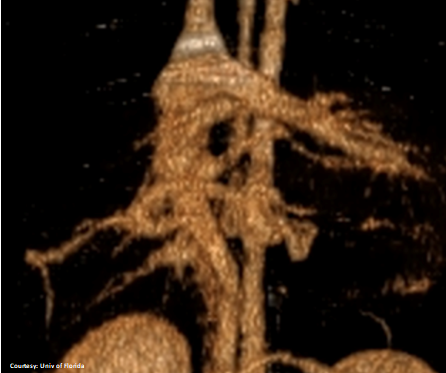

Left Gastric – Left Hepatic Vein shunt with Right Gastric Vein Contribution

Courtesy: Nihon Univ